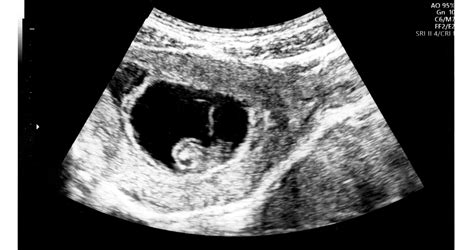

A vetélés diagnózisát nőgyógyászati vizsgálattal és ultrahangvizsgálattal állítják fel. Az ultrahang segítségével megállapítható a terhesség kora, a magzat életképessége (szívműködés), és az esetlegesen a méhben maradt szövetek jelenléte.